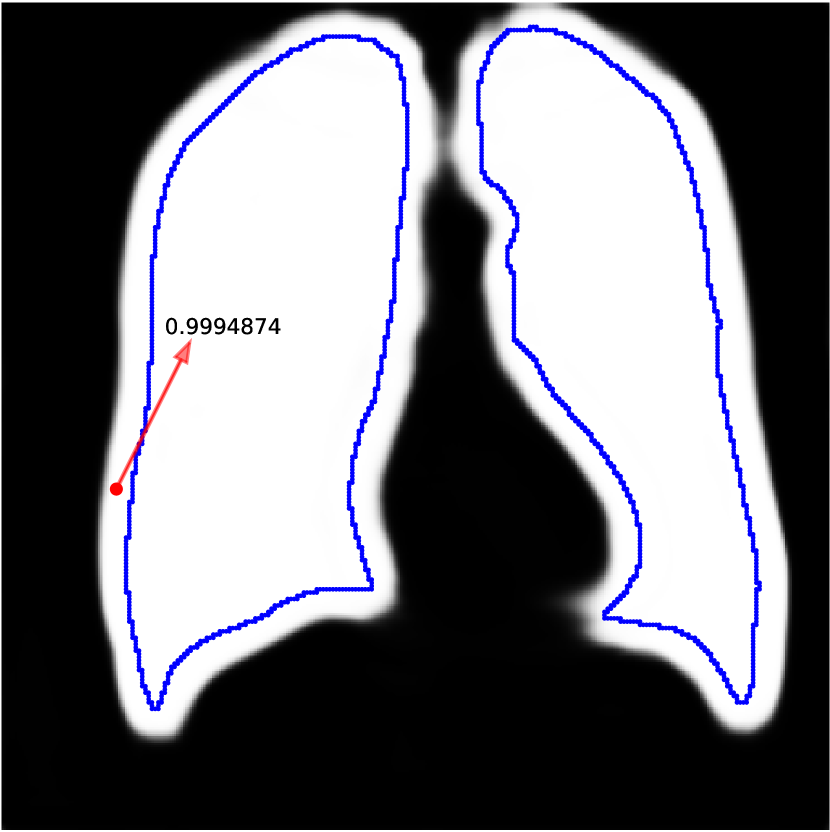

A.3 Illustrative Experiments

Network predictions can be over confident if bias shows up in training labels. Some works (Zhang et al., 2020b; Li et al., 2021) choose to trust the network prediction probability to correct label noises, i.e. they believe predictions with small confidence is likely to be wrong while pixels with large confidence tend to be correctly predicted. However, the network can fit to noisy labels quickly and be overconfident when trained with biased noisy labels. This phenomenon is also observed by Zhang et al. (2016). In Figure A.3(a), we train a network with dilated noises and show its prediction probability map, i.e. the output after sigmoid. The red pixel is predicted as foreground with a high probability , whereas it is actually in background. Therefore, methods based on trusting the network predictions cannot correct this label because the network is over confident. And since the network can fit to noise rapidly, early learning techniques also cannot eliminate this bias. Our method works because we do not trust the network prediction. Instead, we compare it to the clean label in validation set and estimate the bias. We then eliminate this bias in the training prediction. We also show how the prediction probability changes while training the model in Figure A.3(b). It shows that the model can be over confident quickly while training. So methods that employ early learning techniques (Liu et al., 2020; Arpit et al., 2017; Liu et al., 2022) are hard to work under biased noisy labels.